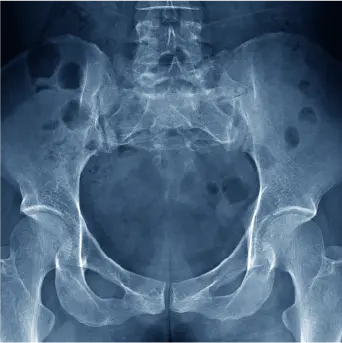

画像検査(レントゲン・CT・MRI)等で大腿骨骨折の診断を行います。緊急手術が必要か医師が判断します。

大腿骨頚部骨折

■ 人工骨頭挿入術(BHA)  ■ 人工股関節置換術(THA)  ■ 骨接合術(ハンソンピン)

大腿骨転子部骨折

■ 骨接合術(ガンマネイル)